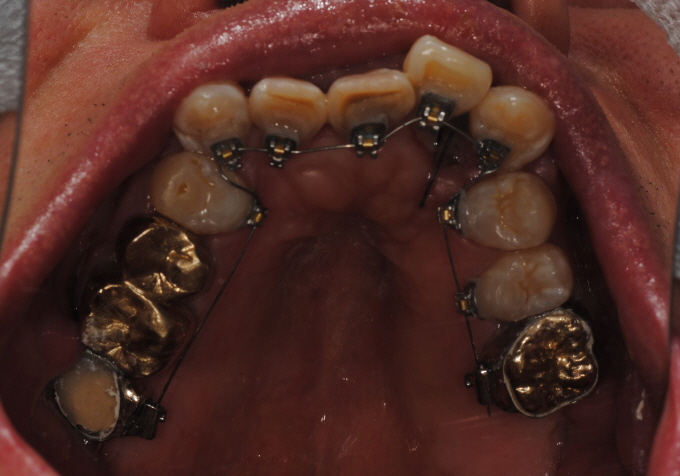

| Fig. 3: 54¼¼ ³²ÀÚ, ÀÌ È¯ÀÚ´Â ¼³Ãø±³Á¤Ä¡·á ÁßÀε¥ ³À̵µ¿¡ µû¶ó¼ Åõ¸í ±³Á¤Ä¡·á ¹æ¹ýÀ¸·Î ÇØ°áÇÒ ¼ö ÀÖ´Â Áõ·Êµµ ÀûÁö ¾Ê´Ù. |